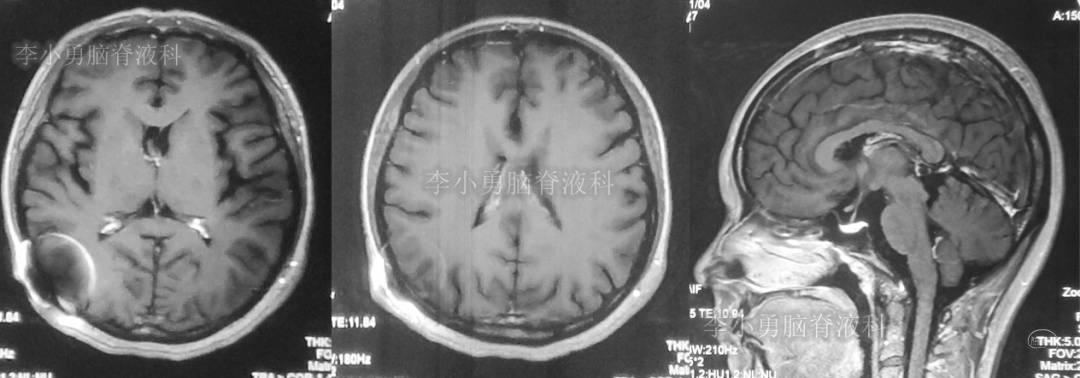

又2天后,即2018年2月5日,为求更好的治疗,患者转到第2家医院:浙江省杭州市的某三甲医院就诊,行头颅增强核磁共振检查(图-2)提示双侧脑室及第三脑室扩张,中脑导水管形态消失,第四脑室无扩张,未见颅内占位病变。

图-2:2018年2月5日头颅核磁